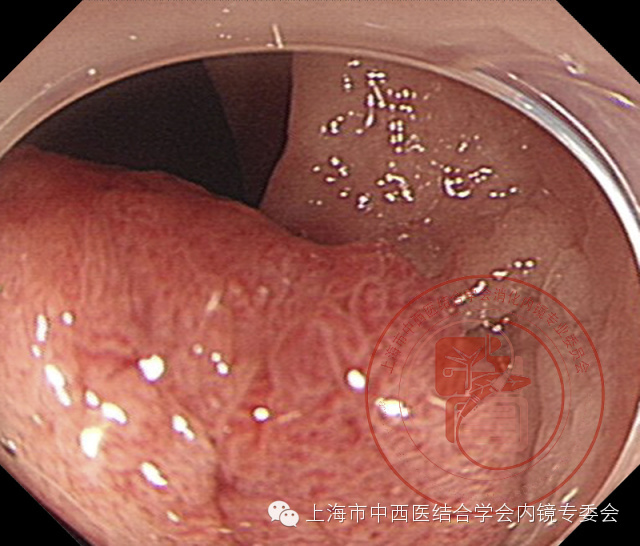

亚蒂息肉

套扎息肉基部